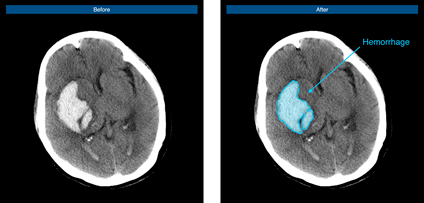

腦出血病例示意圖

腦血管疾病領(lǐng)域作為推想醫(yī)療早期布局的重要疾病領(lǐng)域之一,在近年的北美放射協(xié)會年會(RSNA)上,公司便展示了首款腦卒中AI在研產(chǎn)品,通過不斷研發(fā)和快速迭代“進化”,該產(chǎn)品已可快速判別是否存在出血、高效標注出血病變、準確定位和勾畫出血區(qū)域、快速自動計算出血體積,從而提升醫(yī)生的診斷速度,完善院端急救場景的智能分診和流程管理,并最終為腦卒中患者贏得救治黃金期。